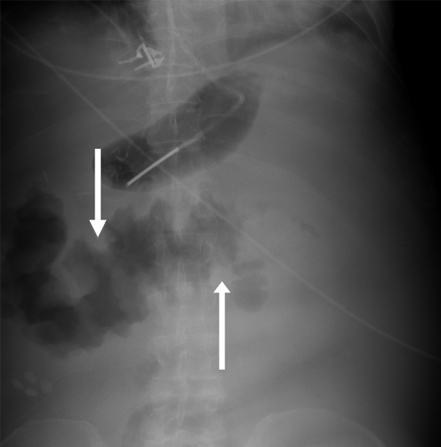

Radiografia abdominal

A radiografia abdominal tem um papel limitado no diagnóstico e na avaliação da isquemia mesentérica aguda.[8][20] Uma radiografia negativa não descarta o diagnóstico.[8] As radiografias simples geralmente estão normais no início do curso da isquemia ou quando a isquemia é leve. Os raios-X não são uma investigação frequentemente usada para a doença isquêmica intestinal.

Com o agravamento da isquemia, a radiografia simples pode mostrar alças intestinais disformes, íleo paralítico ou espessamento da parede do intestino com o sinal da impressão digital, indicando edema ou hemorragia da submucosa.

[Figure caption and citation for the preceding image starts]: Radiografia abdominal simples: demonstra espessamento acentuado da parede do cólon transversal compatível com o achado do sinal de impressão digital (setas brancas)Do acervo do Dr. Amir Bastawrous; usado com permissão [Citation ends].